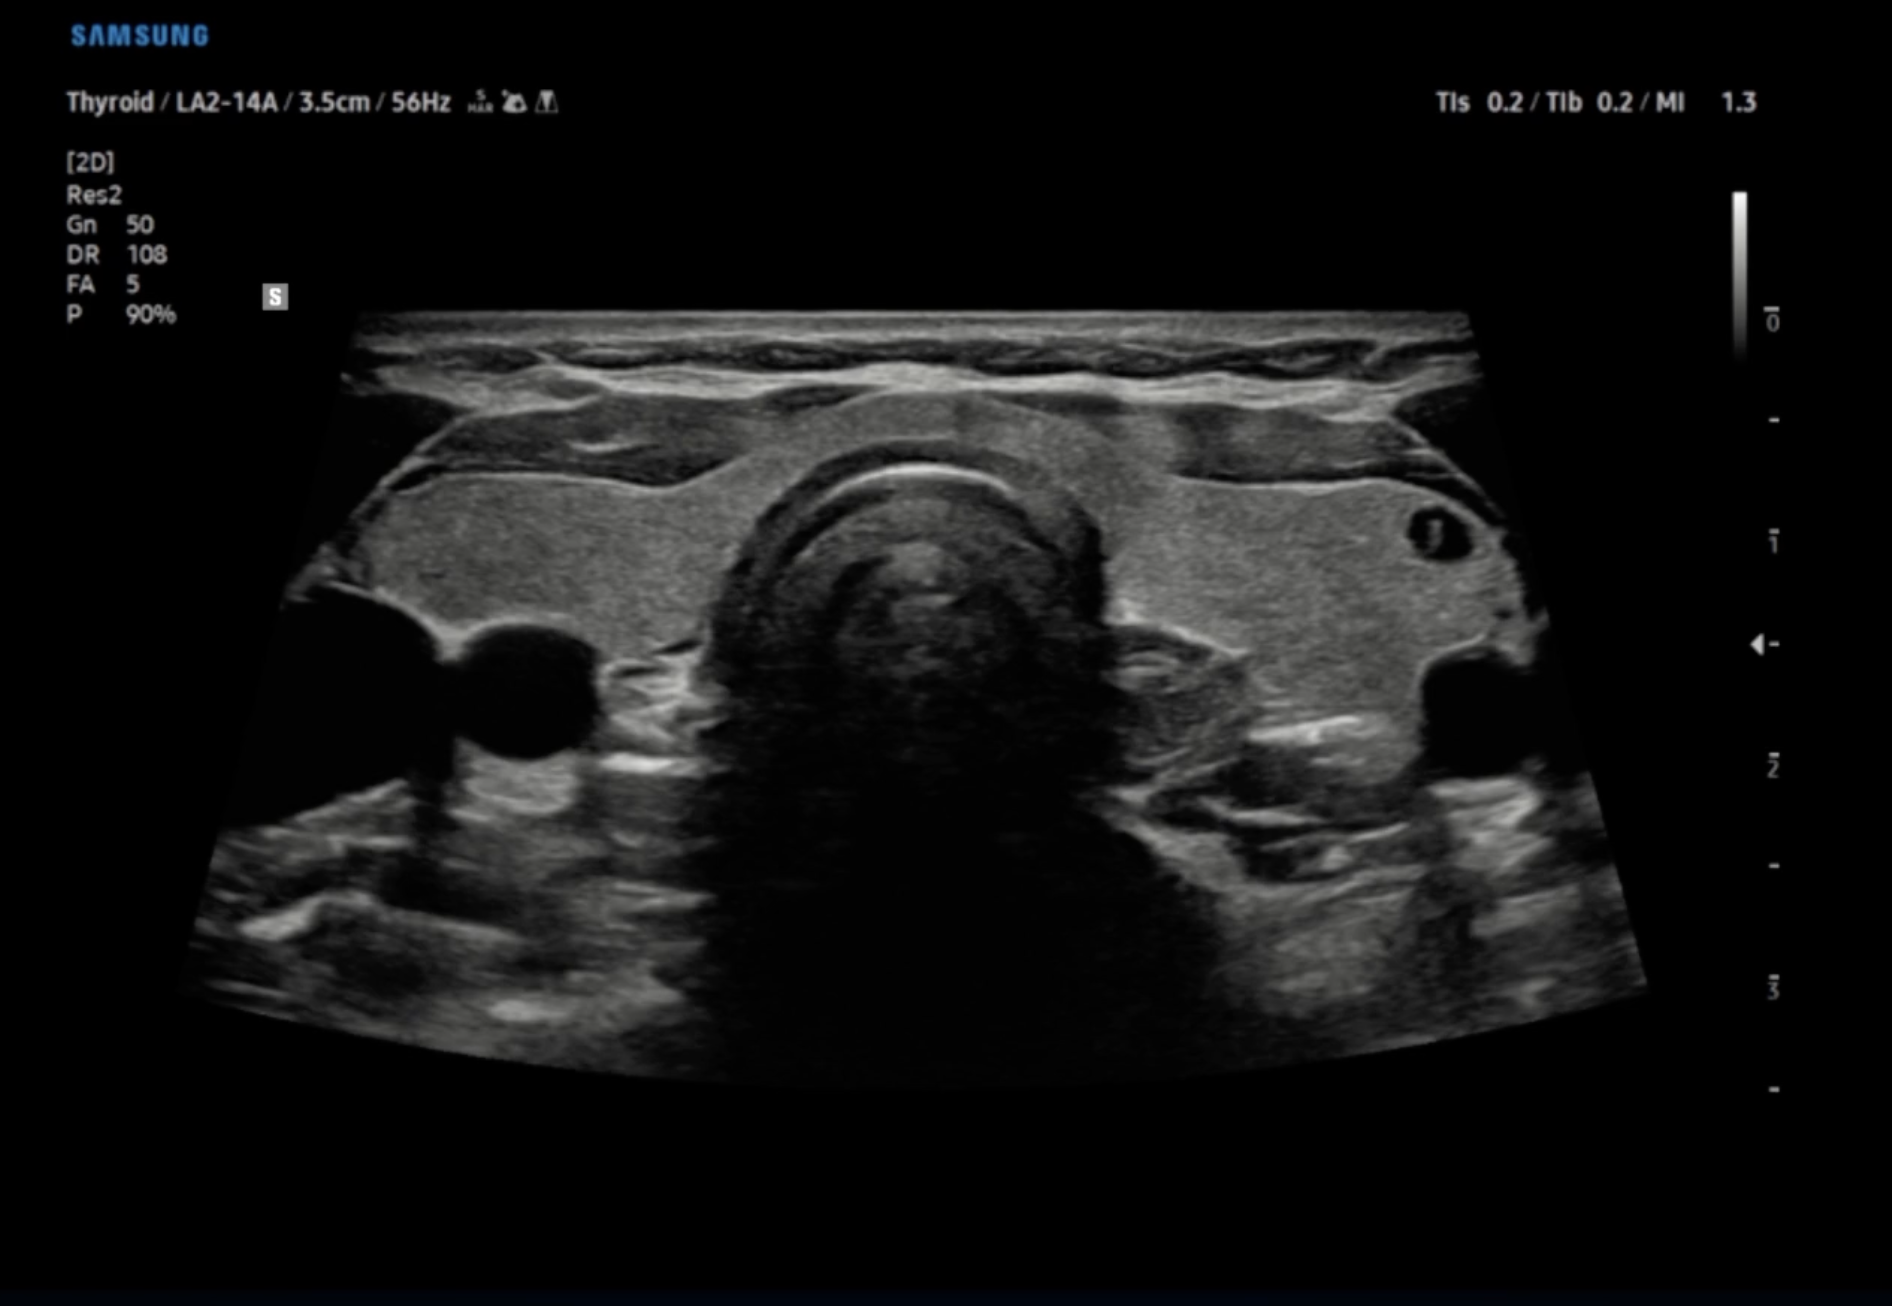

Technische Ausstattung

Entsprechend den Anforderungen unseres breiten Schwerpunktes verfügen wir über alle diagnostischen Möglichkeiten der konservativen Medizin und Diagnostik

Technik

Es ist unsere Grundüberzeugung, daß Technik dem Menschen folgt und und nicht umgekehrt.

Alle technischen Untersuchungen sind Bestätigungsuntersuchungen im Gespräch und der körperlichen Untersuchung erhobener Befunde.

Diese Grundphilsophie stellt sehr hohe Anforderungen an die Hardware. Wir verwenden nur Hardware der renomiertesten Hersteller aus der Schweiz, den USA und Japan.